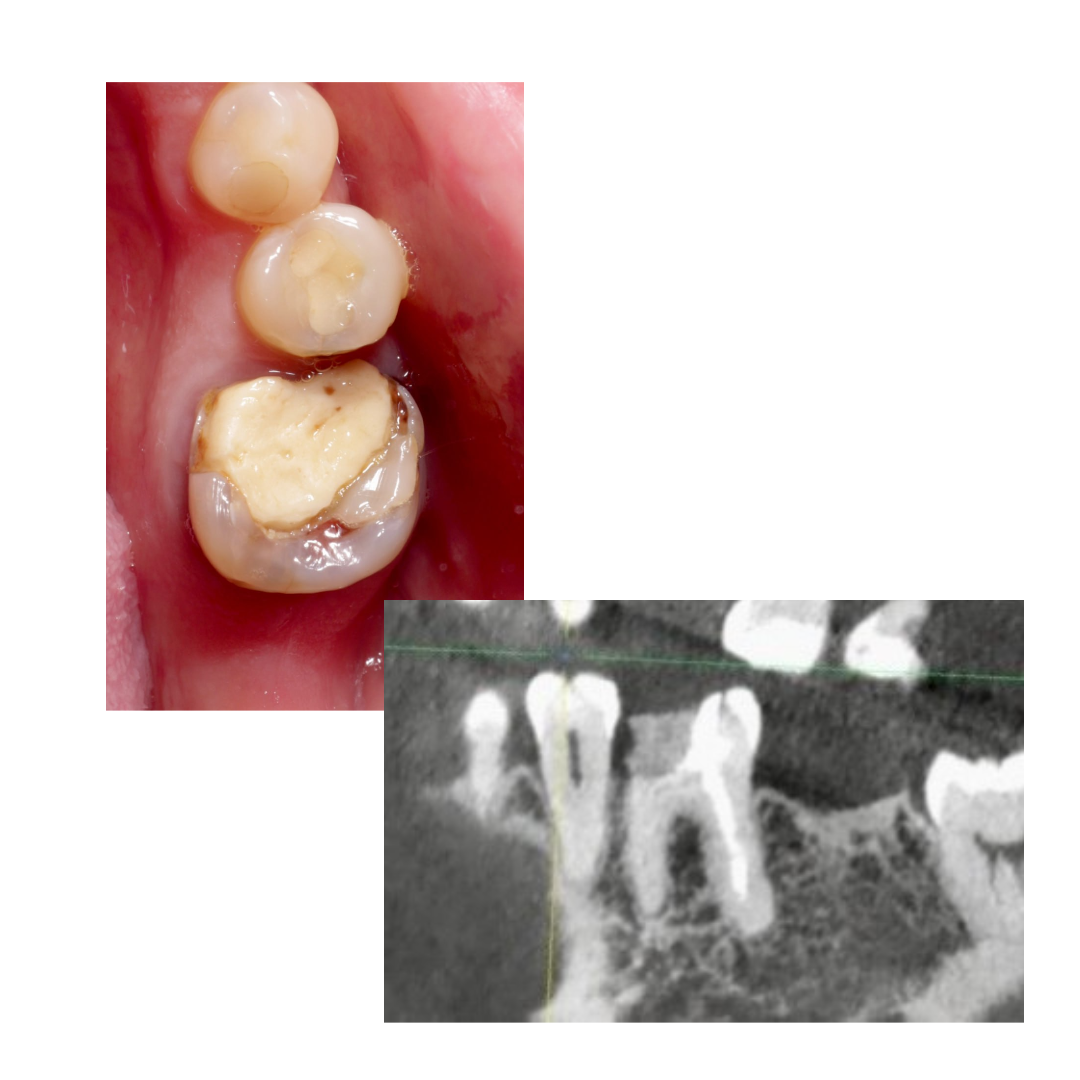

🔹Почистил, отпесочил, понял что можно восстановить. Но из-за инвагинации стенки, решил вот так заморочиться с клином (воткнуть вертикально и зафиксировать)

🔹Щечную и язычную стенку доделал фрихендом. На следующий визит, распломбировка цемента и перепломбировка : биокерамика + непрерывная волна

П.с: ортопеду не показывал ещё, так как план минимум был собрать из пломбы. Как думаете можно в этой ситуации сделать хорошую коронку?